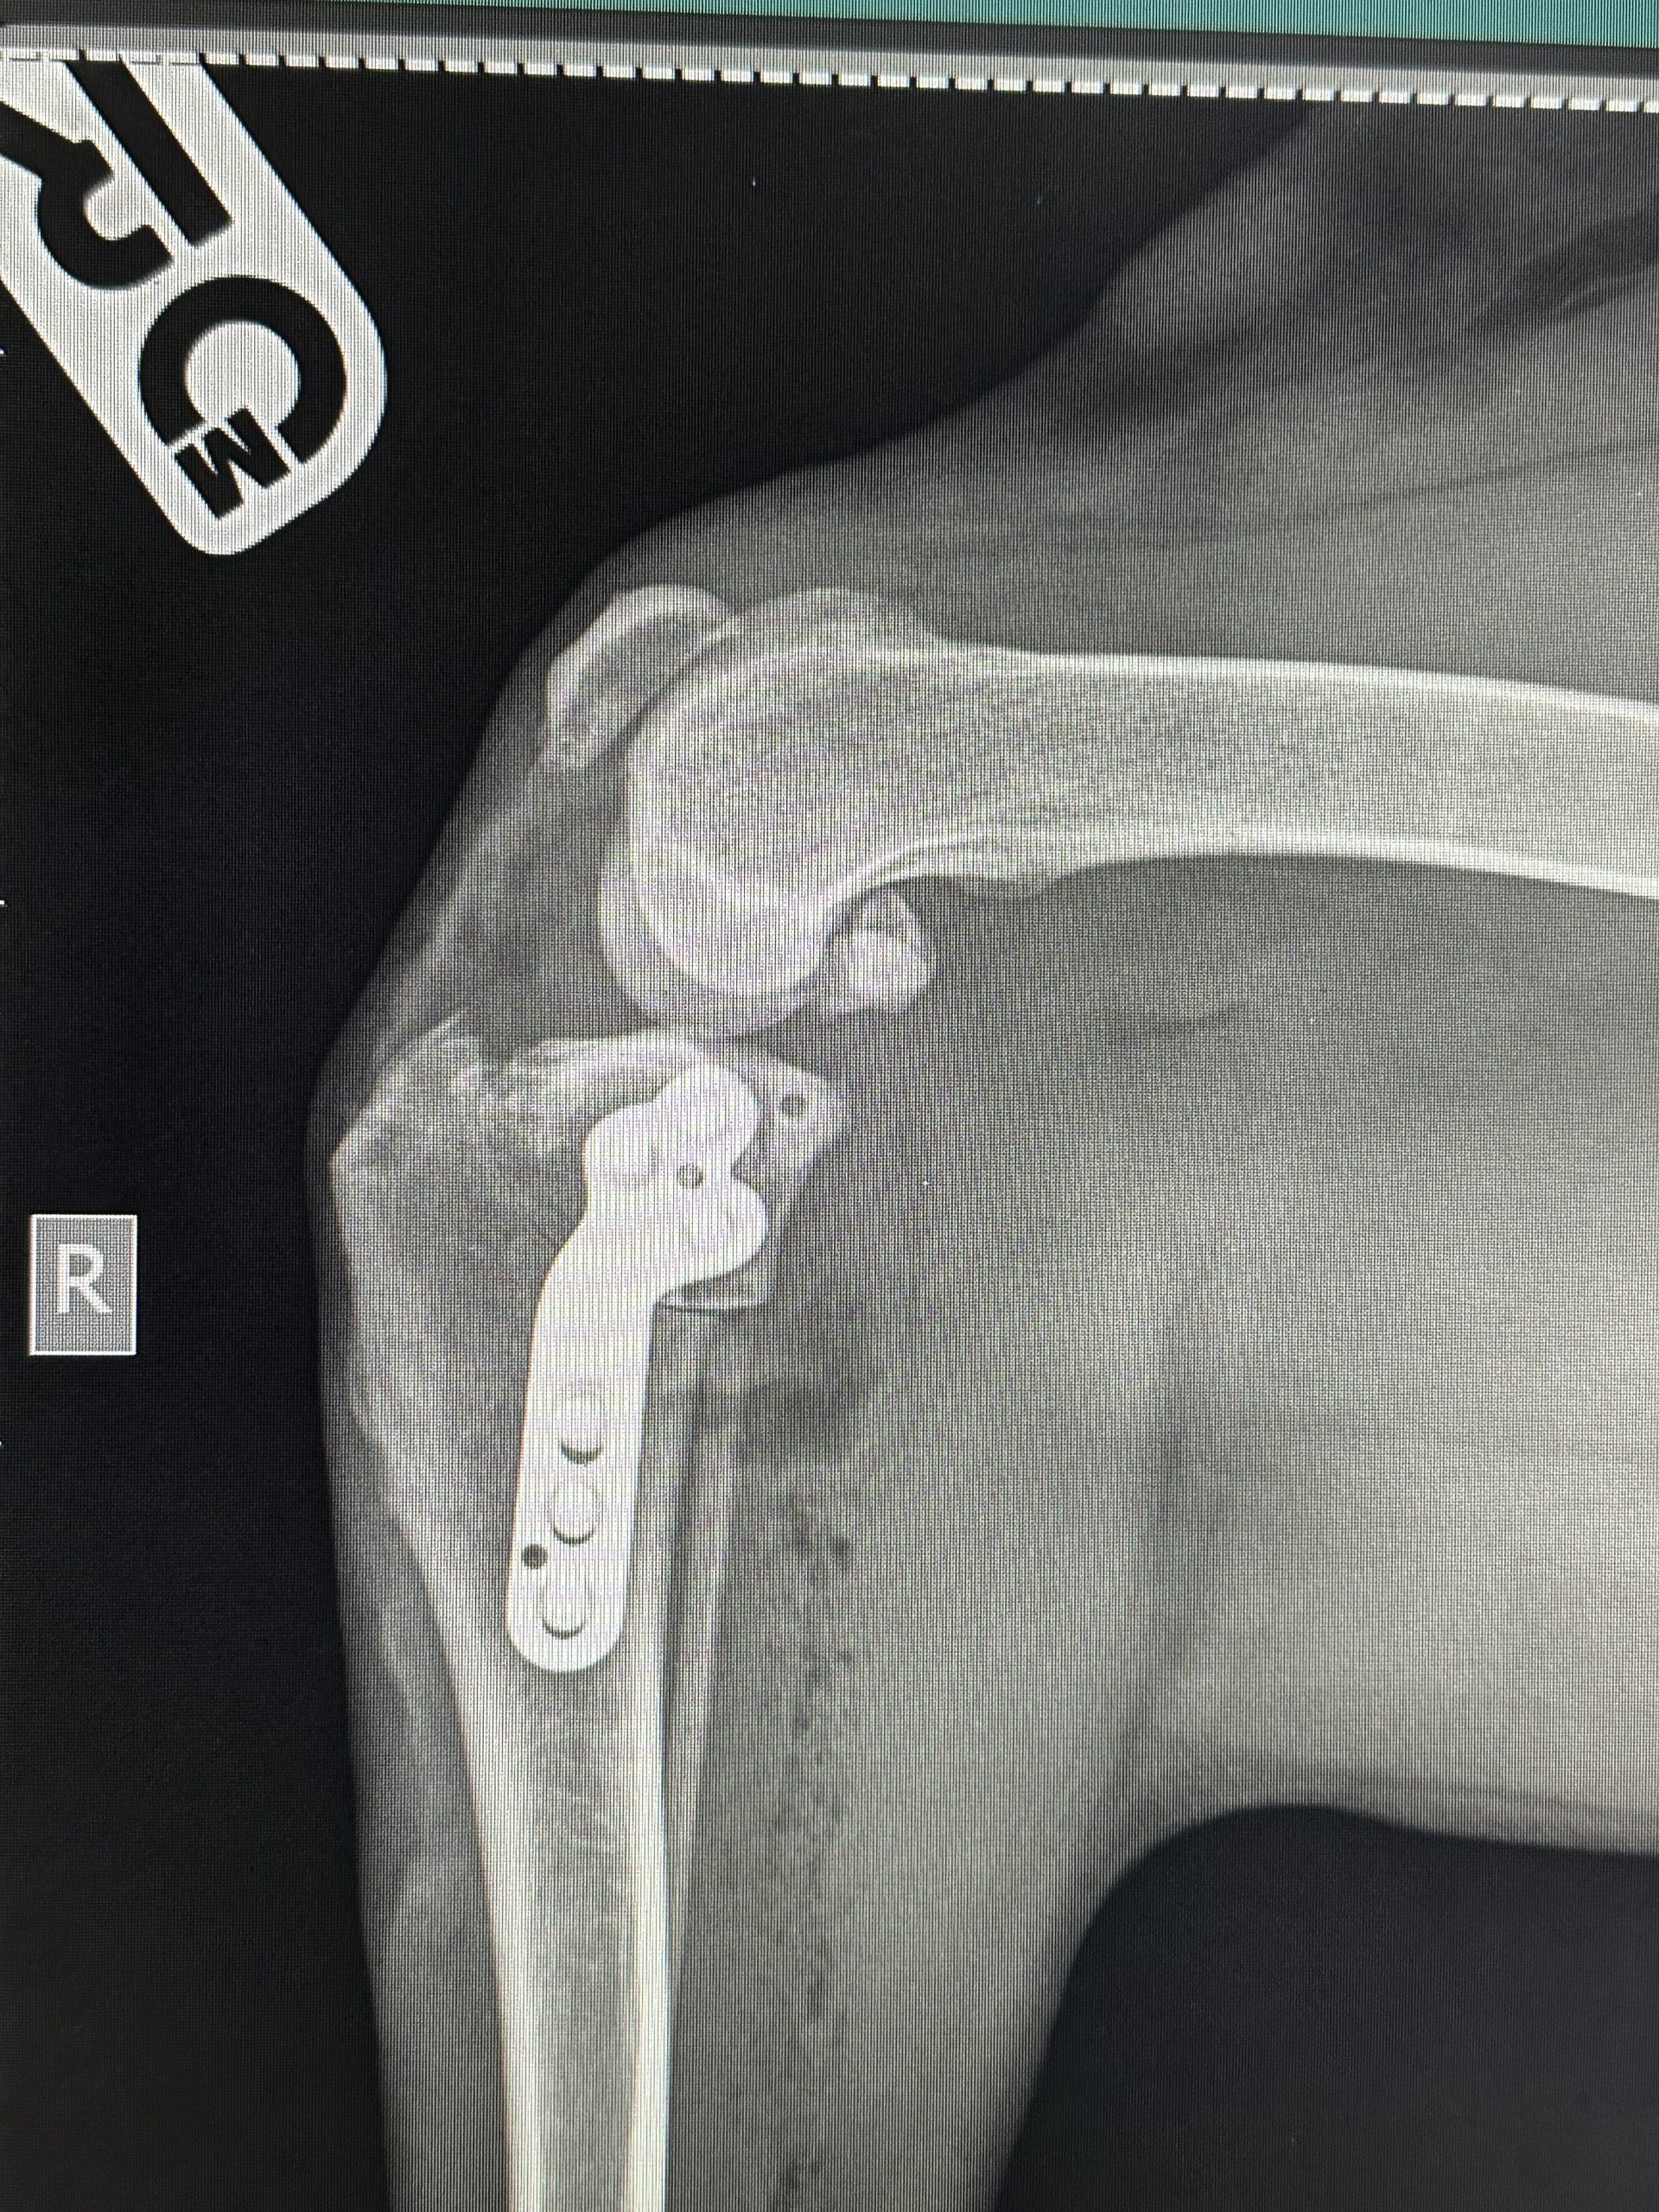

Hirurško liječenje rupture prednjeg križnog ligamenta koljena - TPLO

Za razliku od tradicionalnih metoda koje pokušavaju zamijeniti ili rekonstruisati ligament, TPLO mijenja biomehaniku koljena. Tokom zahvata, hirurg reže tibijalnu ploču (gornji dio goljenične kosti) i rotira je pod precizno izračunatim uglom kako bi se smanjio nagib zgloba. Time se eliminira klizanje femura po tibijalnoj ploči, koje nastaje zbog puknuća ligamenta, i stabilizira koljeno bez potrebe za ligamentom.